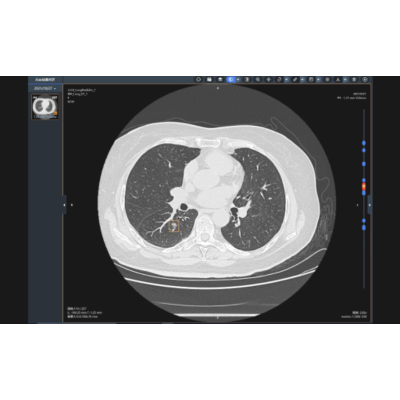

肺结节影像辅助分类诊断

精准识别、分割肺部各类结节灶,输出病灶定位、体积、倍增、密度、形态、征象等多元化参数,进行基于人工智能深度学习的病灶良恶性诊断,肺癌结节灶实现定性诊断。提供随诊复查功能系统,实现多次检查间病灶精准匹配,定量分析,帮助更方便地疾病监测、疗效评估。